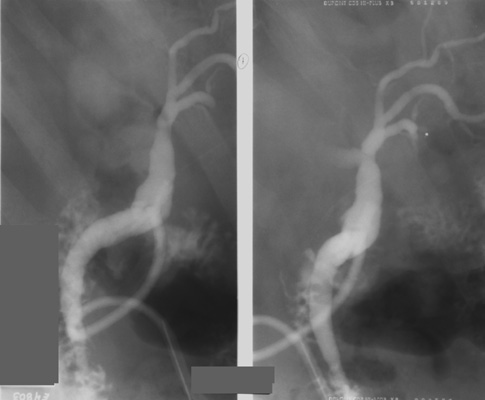

- The patient is rotated into a steep LPO (nearly left lateral)

position and the fluoroscopic table is tilted about 30° head down. In

this position, the left lobe of the liver is dependent, and the left

intrahepatic ducts will fill by gravity. Also, in this position, the

confluence of the right and left hepatic ducts is optimally demonstrated

without overlap.

- The water-soluble contrast agent is slowly

injected by hand while duct filling is monitored by fluoroscopy. When

the branching ducts in the left lobe of the liver have filled and the

right hepatic ducts begin to fill, take the first spot image(s) (2-on-1

format, 109 kVp).